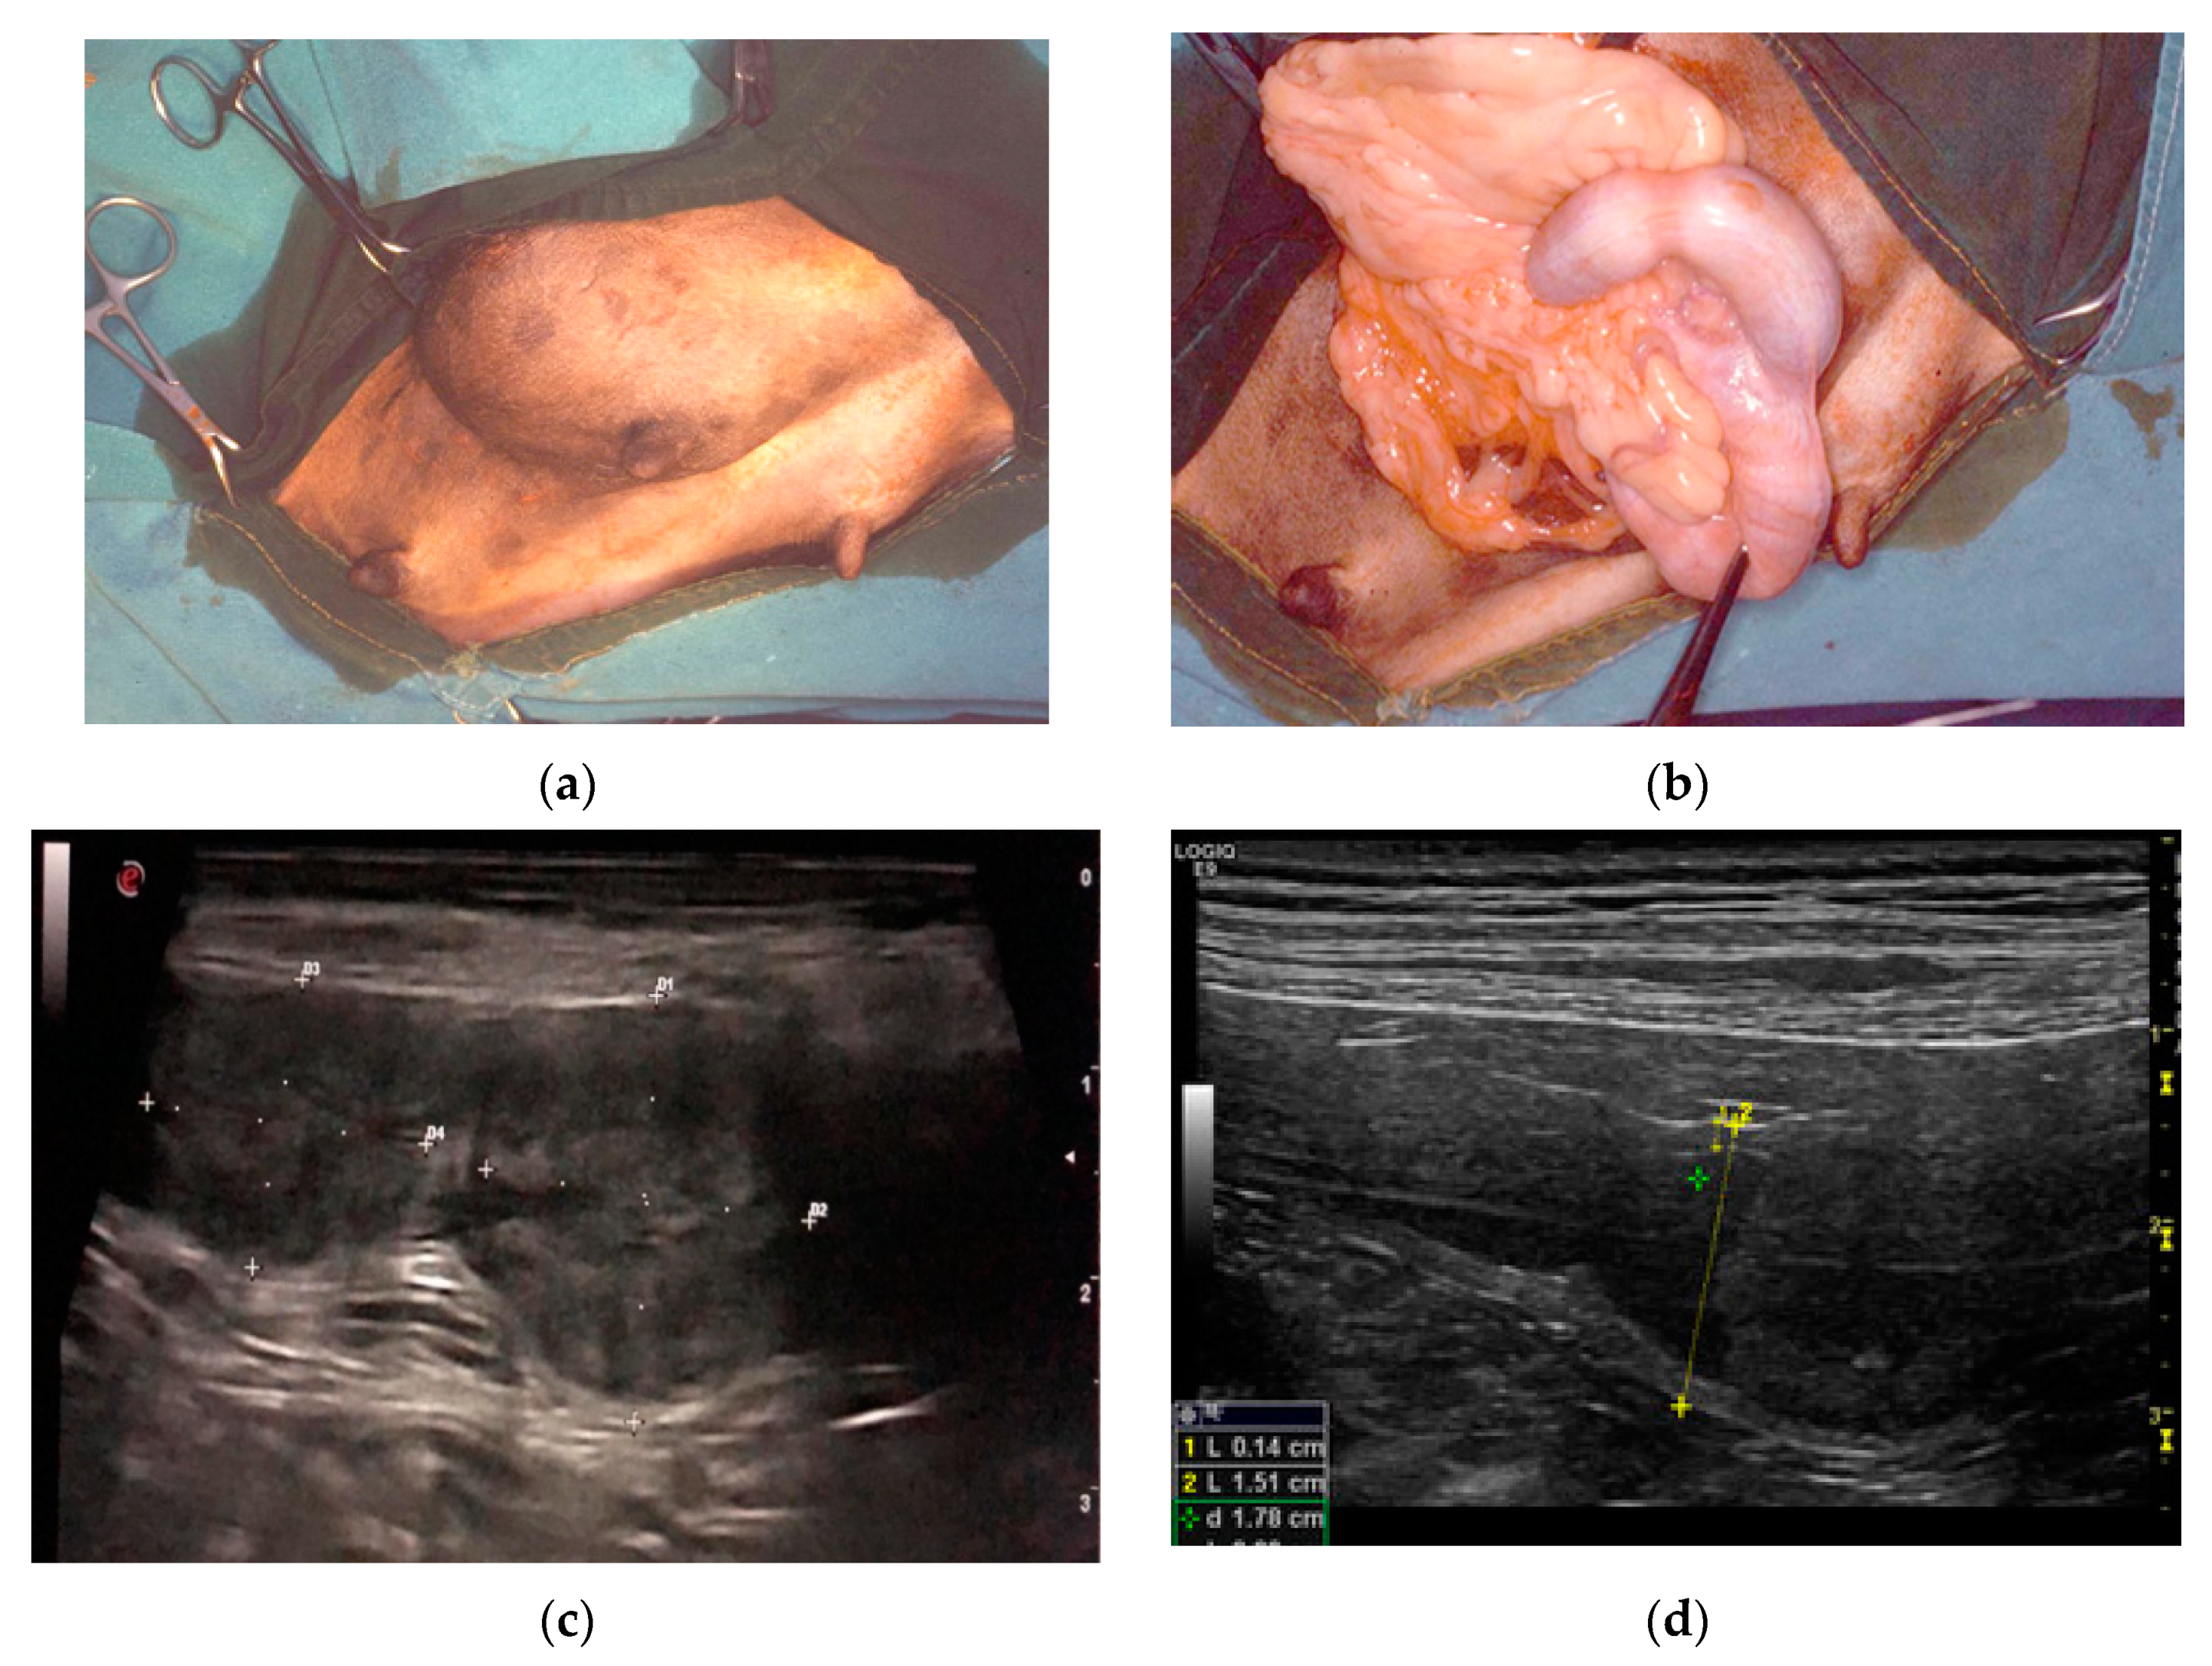

| D1 | Mixed Breed, 1.5 years; history of recurrent clinical pseudopregnancies; in heat 2 months before without mating; asymptomatic; routine anticonception surgery | Longitudinal folds on the uterine serosa; 2 ovoidal uterine swellings in the left and right uterine horn; whitish lardaceous lesions at the swelling: hyperemic uterine mucosa, corpora lutea | 4-layer PEH at swelling level; PEH-like changes on the remaining uterine mucosa; corpora lutea with degenerated lipid-filled luteal cells confirming end of diestrus |

| D2 | Mixed Breed, 6 years; no pregnancies but history of recurrent clinical pseudopregnancies; in heat 2 months before without mating; inguinal hernia; neutrophilia; end of diestrus (P4 = 1 ng/mL); ovariohysterectomy and herniorrhaphy | Longitudinal folds on the uterine serosa; 3 ovoidal uterine swellings in the left uterine horn and 1 in the right; greyish lardaceous lesions at the swelling; hyperemic uterine mucosa, dirty fluid in the lumen; corpora lutea and a large cyst in the right ovary | 3-layer PEH at swelling level; PEH-like changes on the remaining uterine mucosa; diffuse endometritis; corpora lutea with degenerated lipid-filled luteal cells; paraovarian cyst |

| D3 | Pinscher, 2 years; in heat 1.5 months before without mating; asymptomatic; vaginal cytology compatible with diestrus; routine ovariohysterectomy | One ovoidal uterine swelling in the left uterine horn; whitish lardaceous lesion at the swelling; slightly hyperemic uterine mucosa, corpora lutea | 4-layer PEH at swelling level; PEH-like changes on the remaining uterine mucosa; corpora lutea with active luteal cells confirming diestrus |

| D4 | Sicilian hound, 2 years; in heat 2 months before with mating; no pregnancy; end of diestrus (P4 = 1 ng/mL); at ultrasound uterus widening (2 cm) for two adjacent endoluminal mass lesions with suspicion of PEH or placental remnants; ovariohysterectomy | Longitudinal folds on the uterine serosa; 2 ovoidal uterine swellings in the left uterine horn; greyish lardaceous lesions at the swelling; hyperemic uterine mucosa; corpora lutea | 4-layer PEH at swelling level; PEH-like changes on the remaining uterine mucosa; corpora lutea with degenerated lipid-filled luteal cells |

| D5 | Labrador, 5 years; 2 previous pregnancies; in heat 2 months before without mating; end of diestrus (P4 = 1 ng/mL); fluid-filled uterus; at ultrasound uterus widening (2 cm) for an endoluminal mass lesion with suspicion of PEH; ovariohysterectomy | Longitudinal folds on the uterine serosa; one ovoidal uterine swelling in the right uterine horn; whitish lardaceous lesion at the swelling; hyperemic uterine mucosa, mucous fluid in the lumen; corpora lutea and a large cyst in the right ovary | 3-layer PEH at swelling level; PEH-like changes on the remaining uterine mucosa; corpora lutea with degenerated lipid-filled luteal cells; paraovarian cyst |

| D6 | Cairn terrier, 10 months; in heat 1.5 months before without mating; asymptomatic; diestrus (P4 = 20 ng/mL); routine ovariohysterectomy | Longitudinal folds on the uterine serosa; one ovoidal uterine swelling in the right uterine horn; whitish lardaceous lesion at the swelling: hyperemic uterine mucosa, corpora lutea | 3-layer PEH at swelling level; PEH-like changes on the remaining uterine mucosa; active corpora lutea |